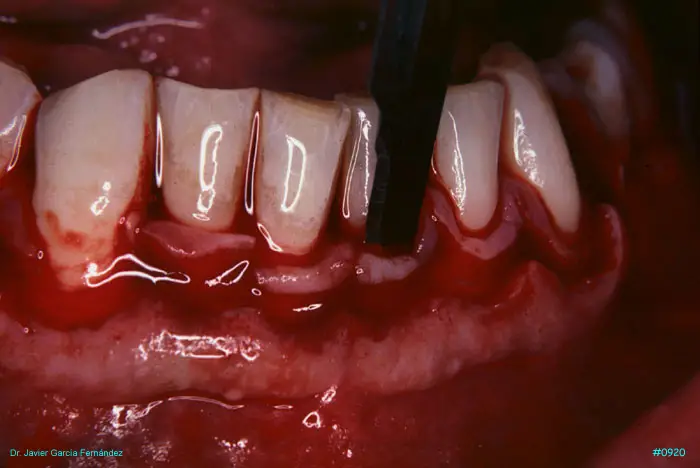

Atlas of Surgical Techniques in Periodontics. Chapter III. Atlas de Técnicas Quirúrgicas en Periodoncia